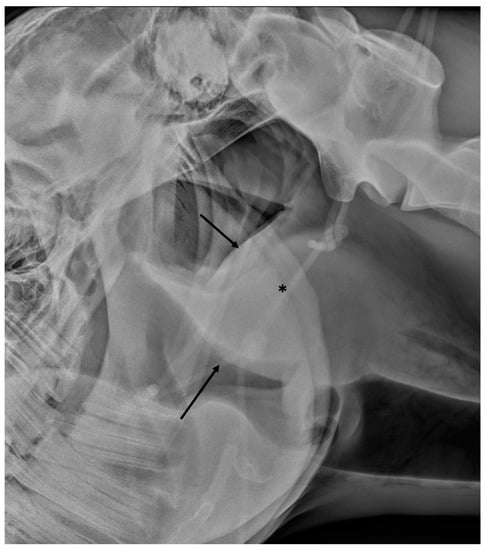

2.1. Radiography

3.4. Temporohyoid Osteoarthropathy